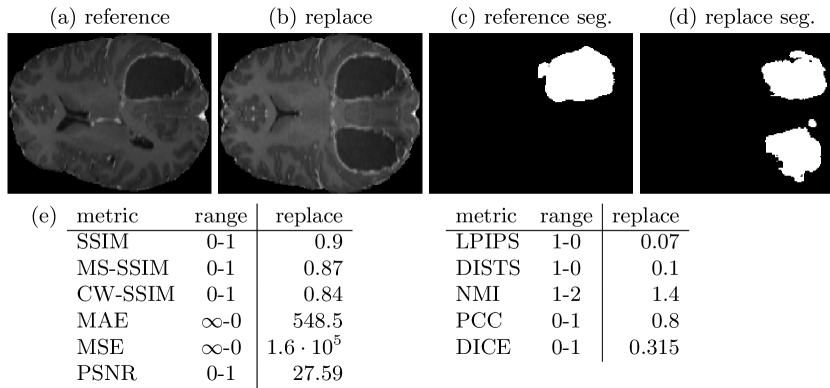

3.5 Pitfall 5: Perceptual and Task-Specific Similarity

Similar to the masking, for medical imaging, a possible tumor is probably one of the most important structures to be correctly synthesized in an MR image of the human brain. However, if there is only a mask of the tumor in the reference image, artificially synthesized tumors in healthy tissue regions in the synthetic image are easily overlooked. Tumors may also be very heterogeneous in their texture and local structure, such that similarity metrics restricted to the tumor region are not informative about the similarity of the tumor type. Therefore, it can be useful to define and perform an important downstream task with the synthetic images. Then the similarity of the synthetic images to the reference images can be assessed by comparing the performance of the downstream task results of both image subsets. If both images lead to very similar results, the synthetic and the reference image appear similar regarding the tested task. In this case, we trained an automatically configuring U-Net based segmentation network [19, 20] on the T1c images of the BraSyn dataset[17] and the whole tumor annotations. The architecture of the U-Net included five residual blocks, with downsampling factors 1, 2, 2, 4 and 4, initially 32 features and one output channel activated by a sigmoid function. As a preprocessing step for training and inference, Zscore normalization was applied to the input images. In Fig. 5 example segmentations are shown and in addition to the previous metrics, the DICE score was assessed from the segmentation results. Especially compared to SSIM, the extra or missing tumors are clearly detected by the DICE score.

In this study we have shown that many types of reference metrics exists with different sensitivity to normalization, misalignment, blurring and masking. Most of these metrics, including SSIM and PSNR, were first developed and designed for 8-bit integer valued natural images for quantifying image quality after image compression or reconstruction. However, now they are often used for assessing similarity between synthetic medical images and real medical reference images. Although SSIM correlates well with human perception, there are specific distortions such as blurring or replace artifacts, where other metrics, such as LPIPS, NMI or a downstream segmentation metric are more appropriate and should be additionally considered. When working with non 8-bit integer images, especially normalization and binning of float-valued data formats must be performed with care and all parameters must be documented, because slight differences have high impact. Further, we showed that misalignment of multi-modal data, that is often used for image synthesis, may impair evaluation. Better pre-registration or the selection of suitable image metrics such as CW-SSIM or DISTS are possible solutions. The use of non-reference metrics, which were shown to detect typical distortions of medical images [21], could approach potential issues with unpaired data. At last, the interpretation of image content plays a central role in the medical domain. Knowledge about regions of interest, downstream detection, segmentation or classification tasks can and should be used to evaluate task-specific similarity. In summary, we recommend to carefully consider the type of expected distortions in the image domain and to select a suitable set of reference metrics. Proper registration, normalization and masking of regions of interest additionally improve the reliability, when evaluating synthetic medical images. {credits}